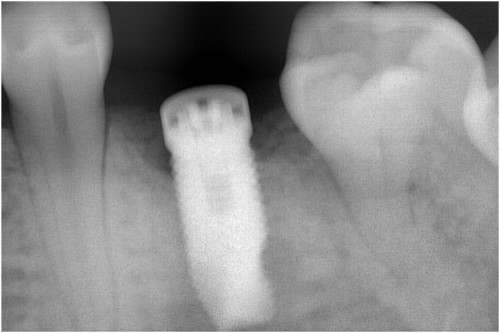

根の先に病巣ができています。

かぶせ物と土台を外します→根の管に詰まっている薬を外します→再び根の管を拡げます

根の管を拡げ終えました→症状がなくなりました→最終的なお薬を詰めます

土台の型を取ります→土台を付けます

歯の周りを削ります→被せ物を付けます